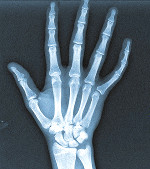

对象全身遍布多处磨损与皮肤撕脱伤。沿前臂有多处撕裂伤,左桡骨有一处骨折。双眼被剜出。

外部检验:年龄与性别不定的人类。身高1.79米,体重62千克。急性白化病。对象没有毛发(雄性征、毫毛或其他)、外阴或第二性征。畸形包括手指有额外骨节及无眼畸形(双眼)。